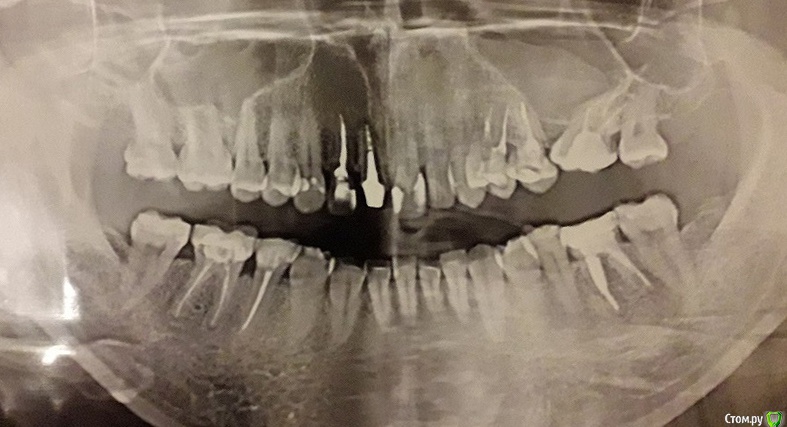

Nata26 Опубликовано 4 сентября, 2020 Автор Поделиться Опубликовано 4 сентября, 2020 К сожалению, с имплантатом всё не очень. 5 дней назад после моих жалоб на боль врач сделал прицельный снимок и там было воспаление. Сама десна выглядит хорошо, свищей нет. После моих просьб сделать хоть что-нибудь, он прописал "Сумамед" 500 по 1 таблетке в день на протяжении трех дней. Сегодня мне сделали панорамный снимок, всё также виден воспалительный процесс в районе имплантата. Он теперь меня отслеживает на протяжении каждых 5 дней. Говорит, что сейчас нужно наблюдать, мол, есть вероятность, что воспалительный процесс пройдет, а если нет — то будет убирать имплантат и заново ставить через месяц. Как вы думаете, есть вероятность, что воспаление пройдет само или мои надежды тщетны? Ссылка на комментарий

Pavel-Pskov Опубликовано 4 сентября, 2020 Поделиться Опубликовано 4 сентября, 2020 Кмк надежды не очень много, но по панорамному точно не сказать на 100 %.. Будем надеяться на лучшее, хотя, если присутствуют боли , то вариант не самый лучший. Ссылка на комментарий

Irouil Опубликовано 4 сентября, 2020 Поделиться Опубликовано 4 сентября, 2020 На мой взгляд имплантат надо удалять Ссылка на комментарий